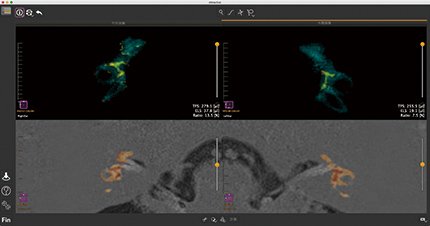

内耳MRI解析

内耳MRI解析T2強調画像で内耳容積を測定し、内耳容積内の内リンパ腫容積と割合を算出します。T2WIとHydrops画像を自動で位置合わせ、重ねて表示できます。